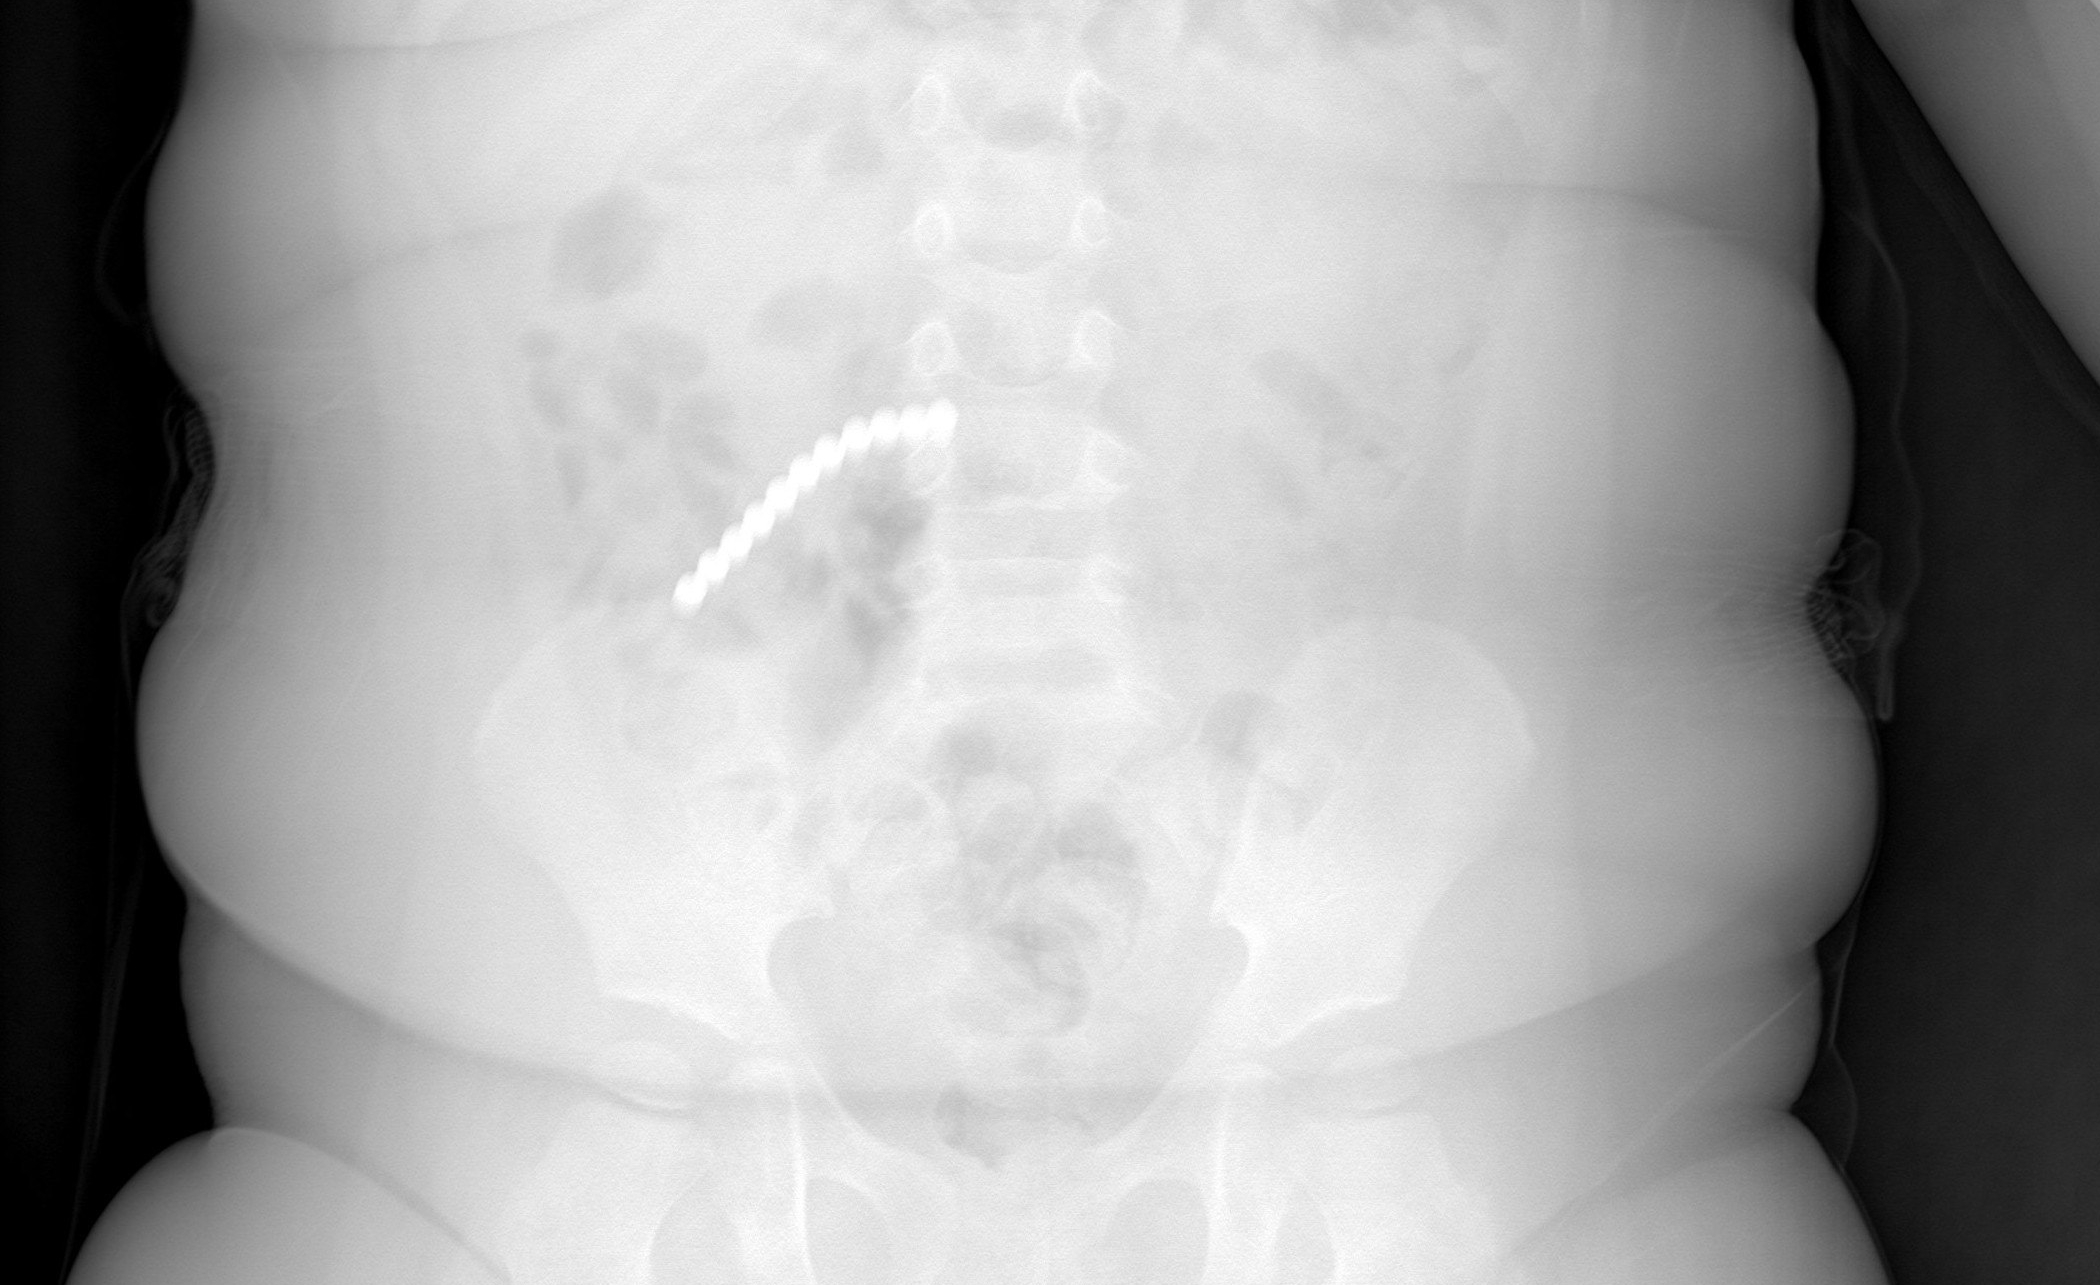

В начале февраля ребенок поступил в Приемно-диагностическое отделение ДРКБ с рвотой и ухудшением состояния. Рентгенография сразу выявила причину — множество инородных тел в пищеварительном тракте. Снимок показал 20 магнитных шариков от неокуба.

Ребенок поступил в Приемно-диагностическое отделение ДРКБ с симптомами рвоты и ухудшением состояния. Рентгенография сразу выявила наличие множества инородных тел в пищеварительном тракте — 20 магнитных шариков.